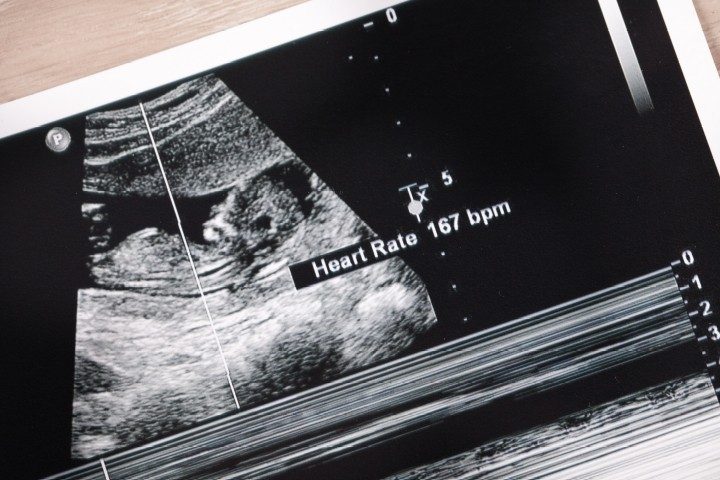

Proponents of the legislation claim that a fetal heartbeat can often be detected as early as six weeks into a pregnancy, while pro-abortion forces claim that those early heartbeats are actually no more than “electrically induced flickering” and not an actual heartbeat.

Hughes, the bill’s other co-author, described the bill in bare-bones fashion: “This bill will say when there’s a heartbeat detectable, that little baby is going to be protected from abortion.”